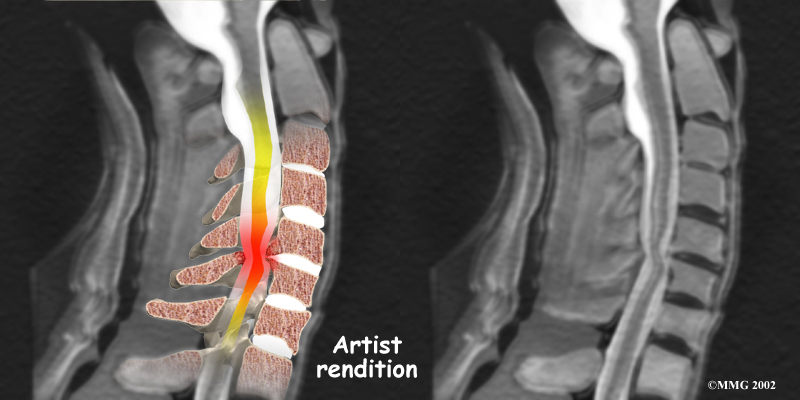

Spinal Stenosis (Cervical Myelopathy)

Stenosis means closed in. Spinal stenosis refers to a condition in which the spinal cord is closed in, or compressed, inside the tube of the spinal canal. Spinal stenosis may be caused by degenerative changes, such as bone spurs pushing against the spinal cord within the spinal canal.

Spinal Stenosis

However, stenosis can also develop when a person of any age has a disc herniation that pushes against the spinal canal. When the spinal cord is squeezed in the neck, doctors call the condition cervical myelopathy. This is an alarming condition that demands medical attention. Cervical myelopathy can cause problems with the bowels and bladder, change the way you walk, and affect your ability to use your fingers and hand.

Cervical Myelopathy